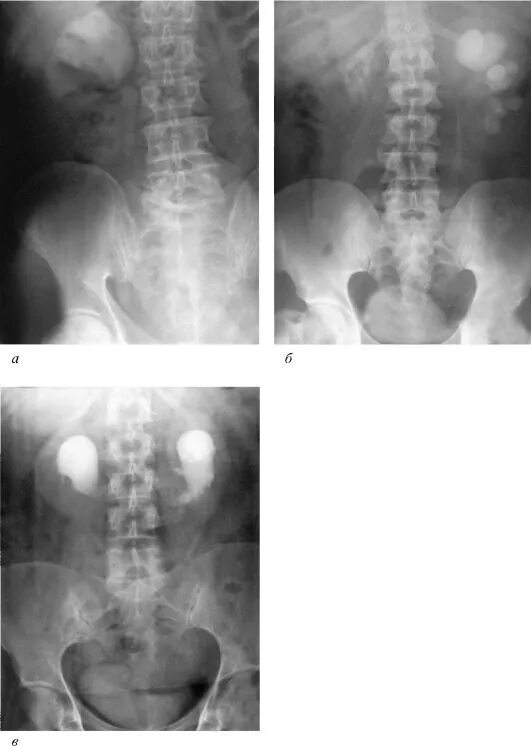

Гидронефроз почки после операции